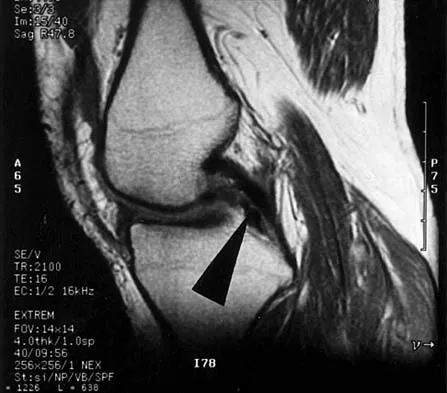

Question 5

A 45-year-old man seen in the emergency department reports a 1-week history of worsening low back pain and a progressive neurologic deficit in the S1 distribution. Examination reveals 2/5 strength in the gastrocnemius. Laboratory studies show a WBC count of 13,500/mm3 and an erythrocyte sedimentation rate of 74 mm/h. Radiographs of the lumbosacral spine show narrowing of the L5-S1 disk space, with irregularity of the end plates. A sagittal T2-weighted MRI scan is shown in Figure 8. Definitive management should consist of

Explanation